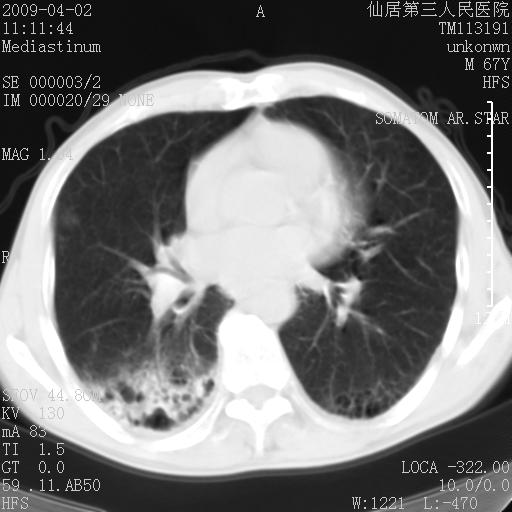

患者老年男性,乏力畏寒来诊,摄胸片示右下肺感染性病变,抗炎两周后复查胸片,无好转有进展。

后做ct平扫表现如下:

考虑右肺炎症可能性大,不除外细支气管肺泡癌

是否还要考虑肺间质纤维化,建议hrct扫描。

考虑间质性肺炎。

病灶呈蜂窝征,纵隔多个淋巴结肿大;肺泡癌需考虑

右肺下叶背段干酪性肺炎。请痰检[emb28]

我认为普通的感染应该可以除外,间质性肺炎可能性较大,但如何解释纵膈的淋巴结肿大呢

考虑双肺间质性改变(间质纤维化?)伴右肺下叶感染。